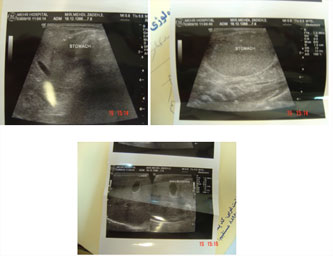

سونوگرافی هم یافته های فوق را تایید کرد تصویر 2 و 3 با توجه به یافته های فوق در

خواست

انجام انما با گاستروگرافین شد که قطر کولون را نرمال نشان داده

است . تصویر شماره 4 ورادیولوژیست بیشتر از کولون عرضی بالا نرفت و بدنبال انمای